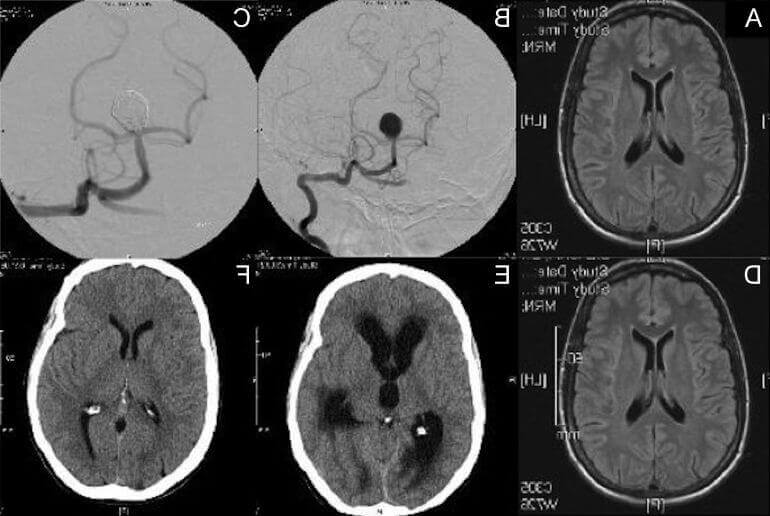

Признаки умеренно выраженной наружная

Признаки умеренно выраженной наружная 113 фото